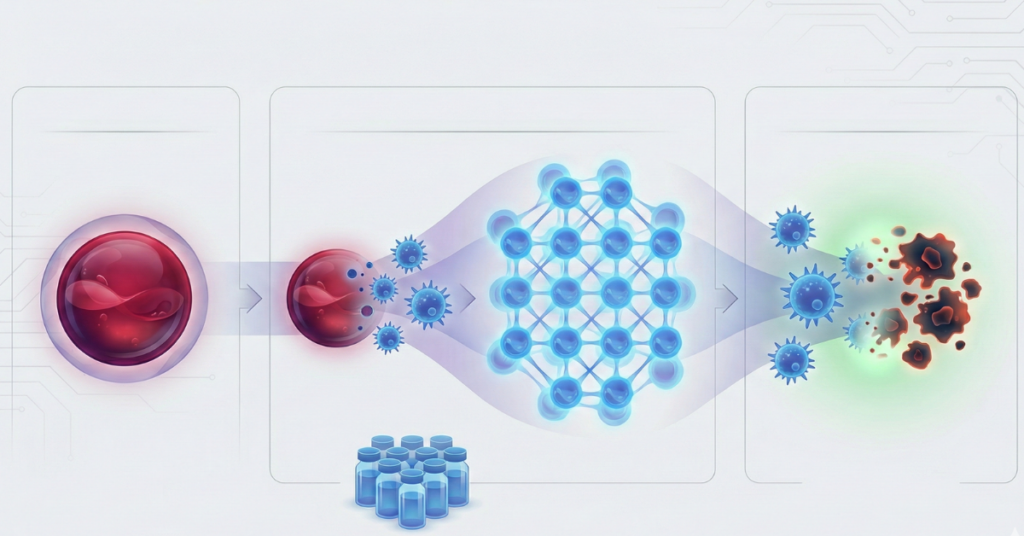

Cilj odloženog presecanja pupčane vrpce, kod zdravih porođaja u terminu, je da se omogući da deo krvi iz pupčanika uđe u novorođenče i poveća zapreminu krvi bebe i snabdevanje gvožđem.

Ovo ima brojne prednosti za bebu, ali smanjuje količinu krvi iz pupčanika koja se može uskladištiti za buduće zdravstvene potrebe bebe, bebine braće i sestara i bebine šire porodice.

Ako imate starije dete kome je potrebna krv iz pupčanika za terapiju, važno je da dobijete veliku količinu krvi iz pupčanika. Neke situacije u kojima se to može desiti su stariji brat ili sestra sa talasemijom ili stariji brat i sestra sa cerebralnom paralizom.